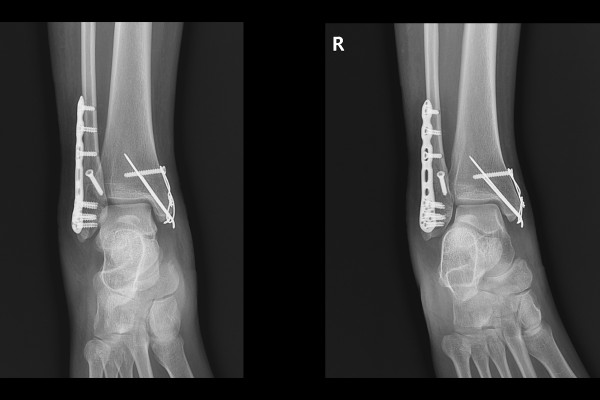

육안으로 보았을 때 발목이 많이 부어 있었고, 지참하신 X-RAY 사진을 보았을 때 안쪽 복숭아뼈(내복사), 바깥쪽 복숭아뼈(외복사)에 골절이 확인되었습니다.

수술 후 X-RAY를 보면 잘 고정된 발목이 확인됩니다.

수술 전/후 X-RAY를 비교해보면 골절선이 잘 맞으며 수술이 잘 되었음이 한 눈에 확인됩니다.